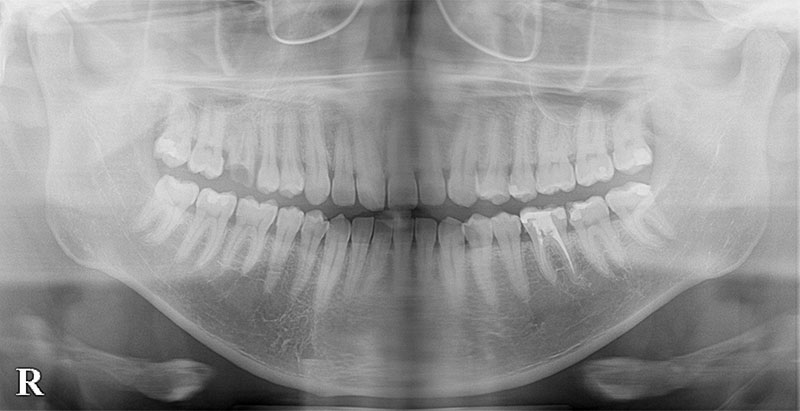

レントゲン写真およびCT画像なのですが、右上6が残歯状態であり歯根破折を起こしている状態でした。しかし歯槽骨から上顎洞底までの距離は十分に認められます。この歯槽骨から上顎洞までの距離がないとソケットリフトなどのオプションの処置が必要になってくるのですが、今回の症例では大掛かりな処置の必要はなく症例の難易度としては比較的イージーな方でした。上顎洞などに関して知りたい方はこちらのページを参照にしていただければと思います。